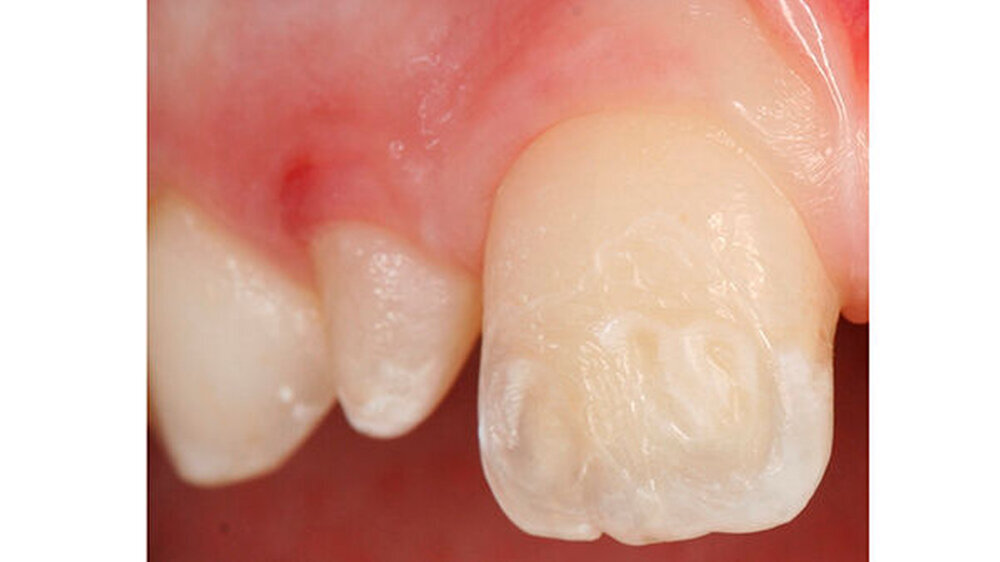

Mit dem Durchbruch der ersten bleibenden Molaren treten dann bisher unbekannte Beschwerden auf wie zum Beispiel eine übermäßig ausgeprägte Kälte-/Wärmeempfindlichkeit. Für manche Kinder wird dadurch nicht nur die Mundhygiene sondern auch die Nahrungsaufnahme erschwert. Zusätzlich bricht oft schon in der Durchbruchs-Phase der Schmelz ein (Abbildung 1), was die Überempfindlichkeit in teils akute Zahnschmerzen übergehen lässt.

Das klinische Bild der MIH reicht von einem bis zu vier betroffenen Molaren, nur selten sind alle Zähne in ähnlicher Ausprägung geschädigt [Weerheijm et al., 2001]. Die bleibenden Frontzähne können ebenfalls betroffen sein, diese weisen allerdings in der Regel keinen Schmelzeinbruch auf und sind selten bis gar nicht überempfindlich [Weerheijm et al., 2001] (Abbildung 2).